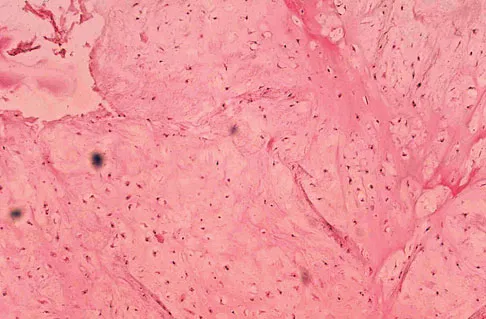

Where is the underlying defect in a rhizomelic dwarf with the findings shown in Figure 5?

Explanation